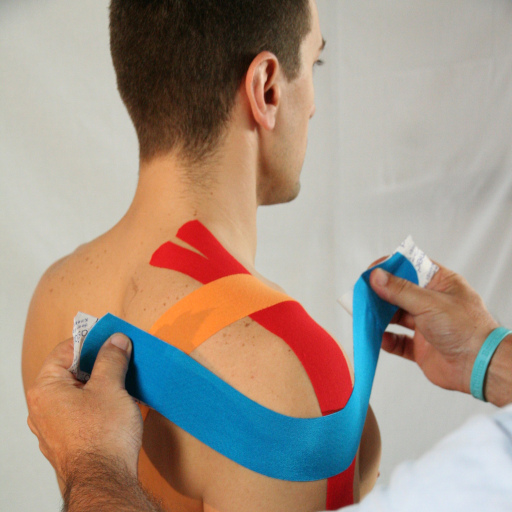

Il taping Bellia System aiuta il trattamento del conflitto della caviglia

Seguendo i principi della tecnica di taping kinesiologico Bellia System possiamo utilizzare in maniera sinergica al trattamento riabilitativo alcune tecniche di taping elastico:

- Nella fase infiammatoria con paziente senza carico podalico o carico parziale con stampelle: si realizzerà una tecnica drenante di linfo taping. Si sceglierà la lunghezza del nastro in base alla condizione dell’apparato emo linfatico del paziente.

2. Nella fase di riabilitazione funzionale con paziente con carico totale e autonomia quasi completa: si realizza una tecnica decompressiva articolare e se servirà potrebbe essere utile una staffa di sostegno calcaneare.

3. Nella fase di rientro lavorativo o sportivo: sarà realizzata una tecnica stabilizzante multiassiale per garantire un supporto all’articolazione durante le sollecitazioni date dal carico.

Le foto di questi bendaggi sono tratti dal libro:

Bellia Rosario – Manuale di taping kinesiologico per la traumatologia sportiva moderna – ed. Nuova Piccin – 2017 Padova